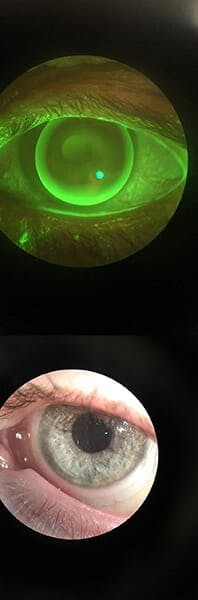

The back surface of the lens is designed to fit the contour of the protrusion, much like fitting a hat to your head. A contact lens is the most highly effective way to manage the visual needs of someone with keratoconus and 90% of all cases can be managed this way indefinitely. For many years, the only contact lens option to improve vision for keratoconus was hard contact lenses, now referred to as gas permeable contact lenses.

With advancements in contact lens technology, there are now many different types of contact lens options available and our skilled optometrists will narrow down which one is right for you. New specialized gas permeable lens designs and manufacturing techniques have greatly improved vision and comfort compared to older gas permeable designs. In addition, specialty soft, hybrid, and scleral lenses are available, providing excellent visual results and improved comfort for patients intolerant to gas permeable lenses.